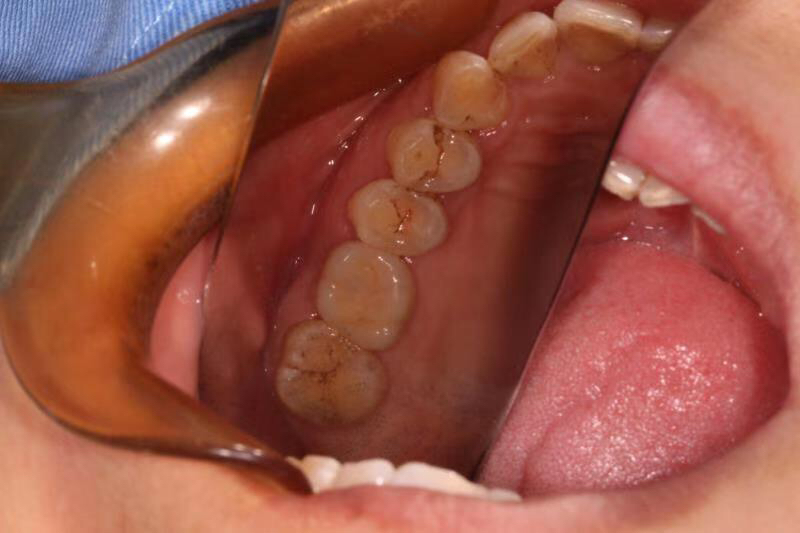

患者中年女性,左上6号牙因根尖炎症过大导致松动后拔除,因炎症过大,稳妥起见未进行即拔即种的种植方式,我们采取了先拔牙,3个月后种植的治疗方案。

由于骨量不足,我们术中进行了上颌窦内提、植骨、盖膜、CGF覆盖,最大程度的保证了种植的成功率和使用强度。